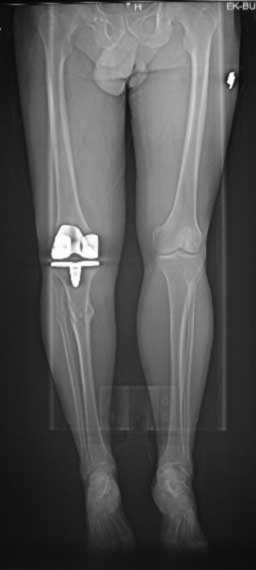

Пациент 8 мес после операции ТКА, в анамнезе неправильно сросшийся

перелом голени, коррекция оси (снимки прилагаются).

В настоящее время имеется разгибательная контрактура 10/5/0, на

операционном столе было 90/0/5, на момент выписки движения 50/0/0 в

надежде на дальнейшую разработку. До эндопротезирования 40/10/0.